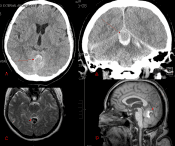

Dr. Brisman is proficient in the use of minimally-invasive, neurosurgical procedures including:

- Stereotactic Radiosurgery

- Gamma Knife®

- CyberKnife®

- Novalis Tx®

- Brain Tumors

- Acoustic Neuromas

- Meningiomas

- Brain Metastases

- Gliomas